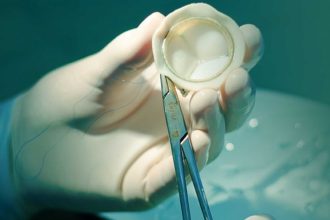

تعتمد العلاجات على نوع المرض وشدته، وتشمل الأدوية للتحكم في الأعراض أو تحسين وظائف القلب، والقسطرة لتوسيع الصمام الضيق، أو الجراحة لإصلاح أو استبدال الصمام المتضرر.

أفضل أنواع صمامات القلب أيهما تختار الطبيعي أم الصناعي؟

قد يصل بك الطريق أحياناً إلى طريق مسدود…

تغيير صمامات القلب | أنواع الجراحات والخيارات المتاحة

تتعدد الأمراض والمشاكل التي يمكن أن تصيب القلب،…

الصمام المعدني للقلب | مميزاته وعيوبه والمشاكل المصاحبة لتركيبه

الصمام المعدني للقلب، هو الخيار الثاني لمرضى صمامات…